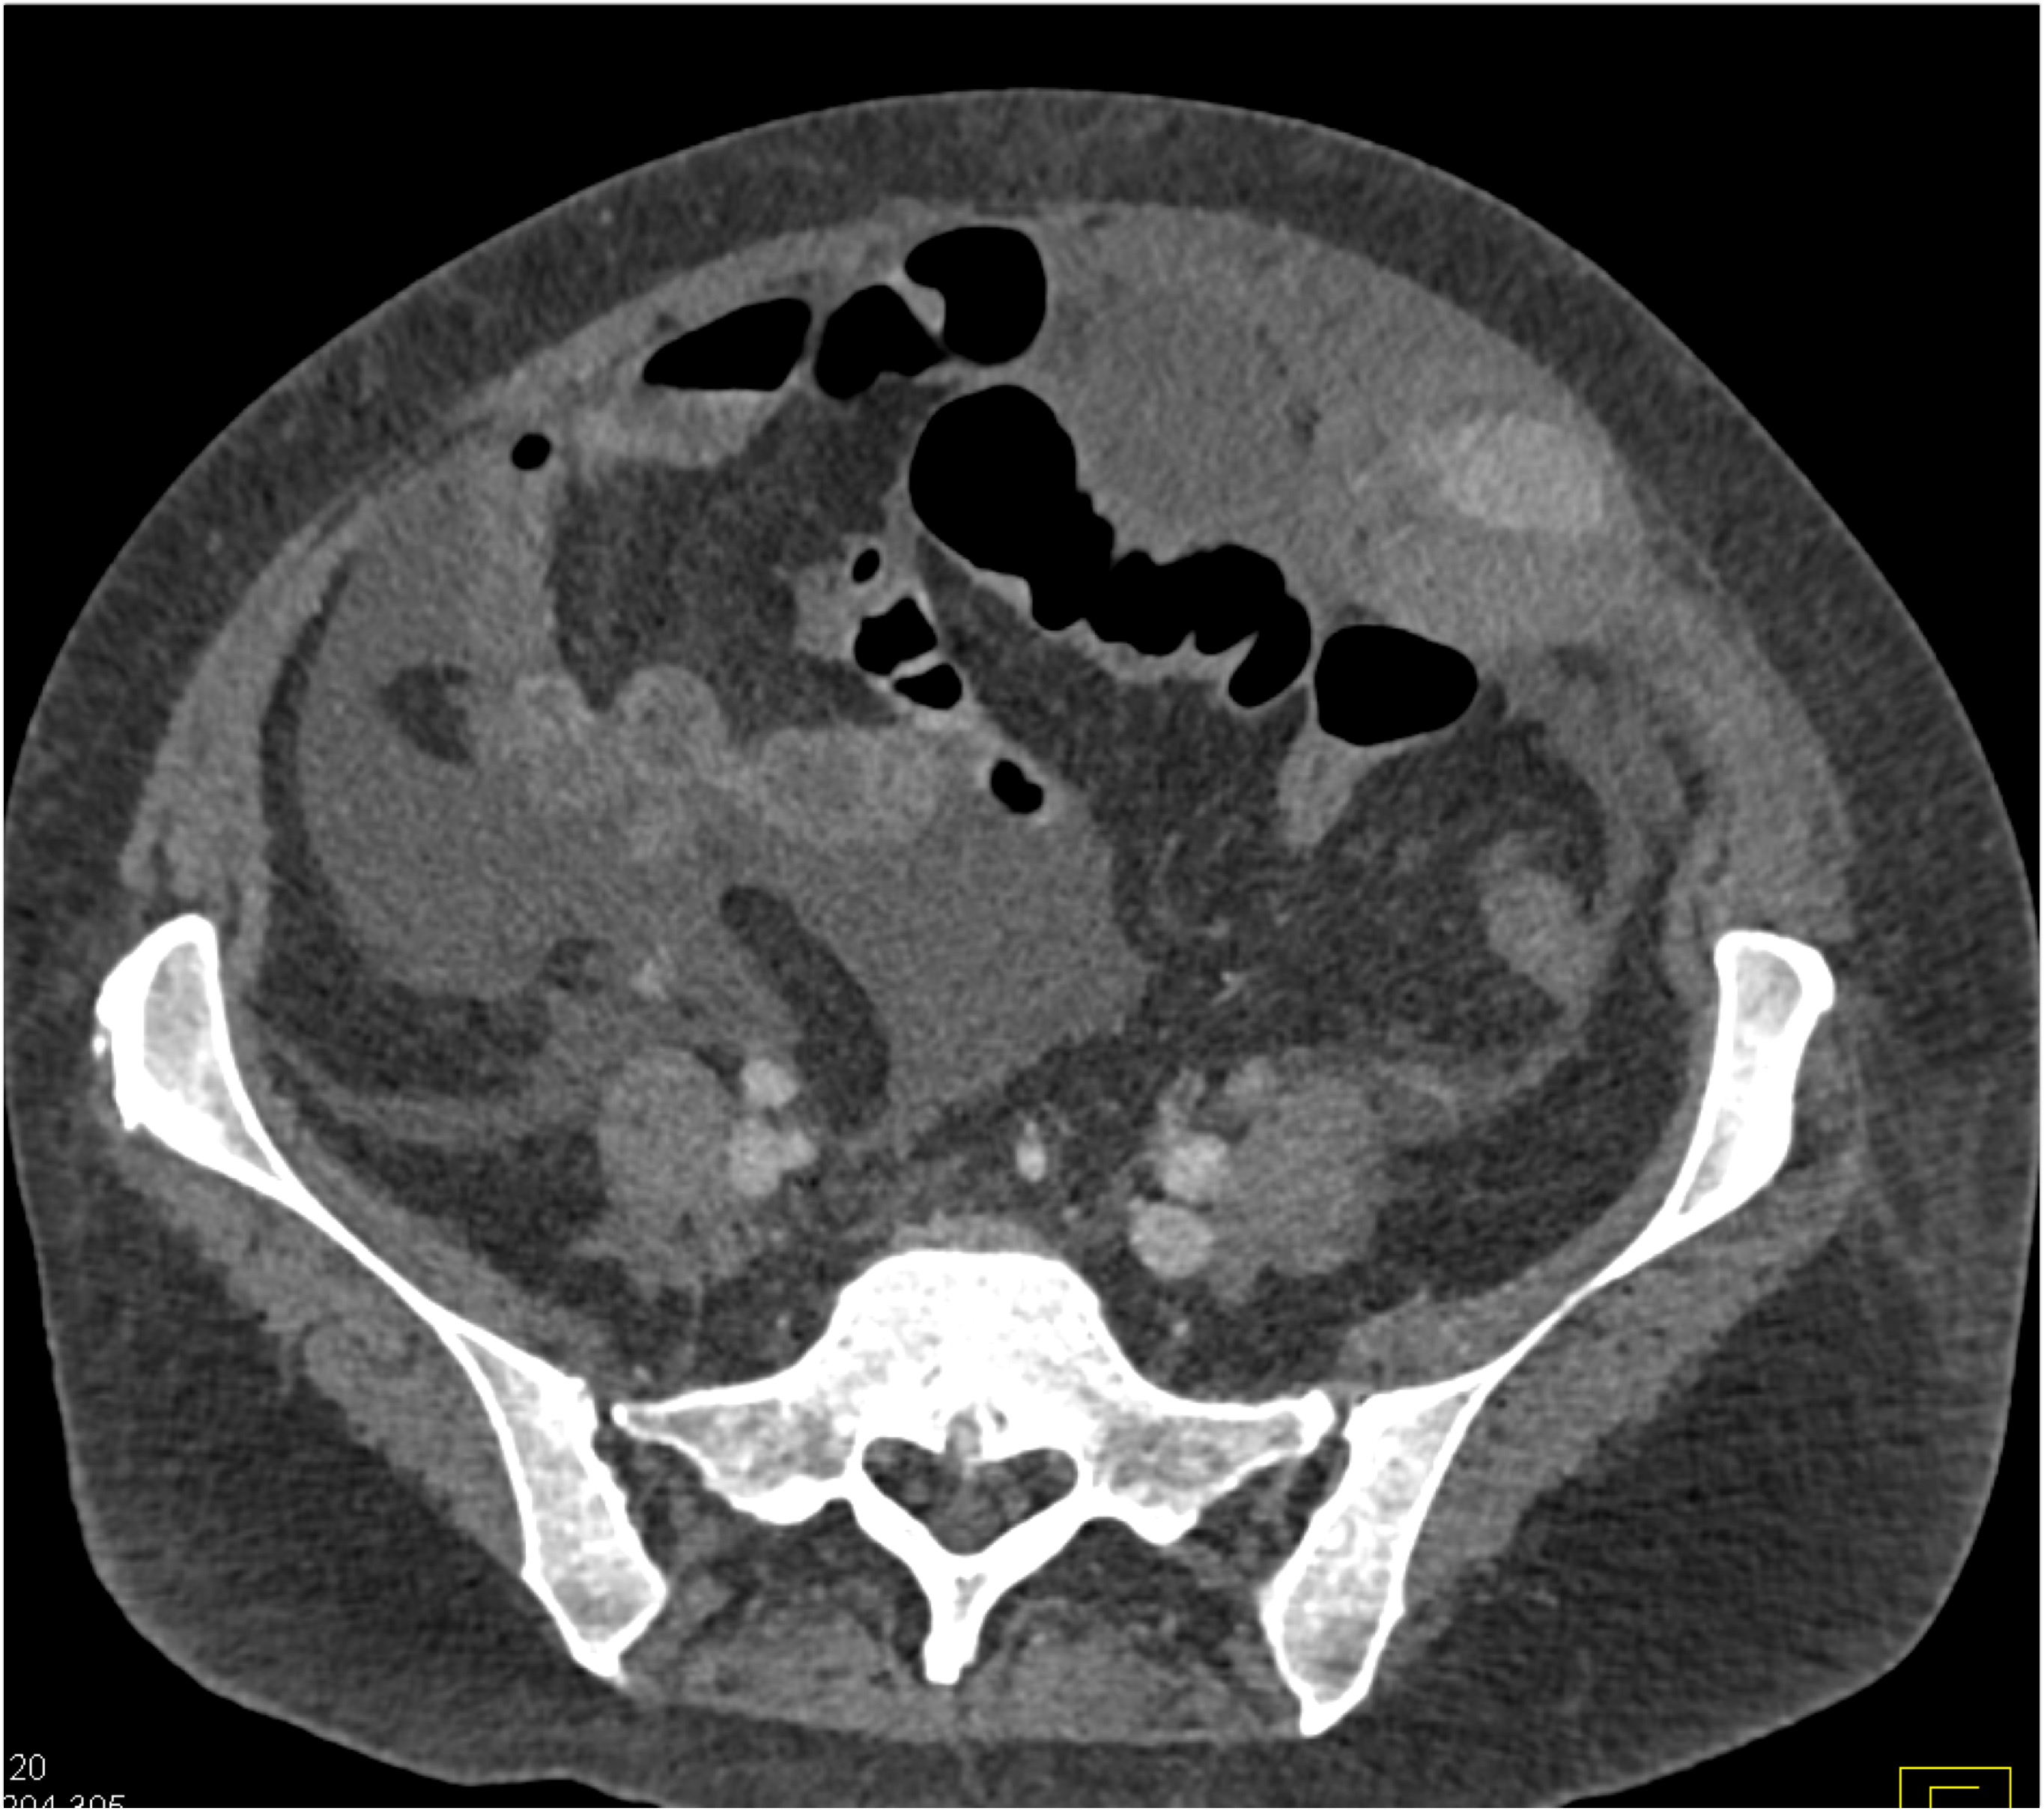

2) In this patient with a palpable right abdominal wall mass the best dx is?

rectus sheath hematoma

lymphoma

desmoid tumor

metastatic renal cell carcinoma